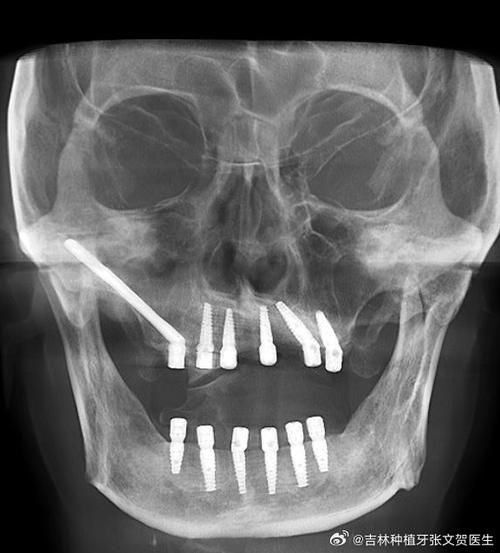

颧骨植牙的技术原理是通过外科手术,将特制的长种植体(长度通常可达30-55mm)从口腔前庭切口进入,穿过上颌骨,最终植入颧骨主体内,种植体的头部(基台)仍位于牙槽嵴顶,用于连接牙冠,而尾部则固定在颧骨内,通过颧骨的支撑力分散咀嚼力,从而恢复牙齿功能,这种种植方式也被称为“颧骨支抗种植”,其核心优势在于无需依赖上颌后牙区的牙槽骨,避免了复杂的骨增量手术(如骨移植、上颌窦提升等)。

术前需进行详细的影像学检查,如锥形束CT(CBCT)和三维重建,明确颧骨的骨量、密度、解剖结构(如颧牙槽嵴、上颌窦位置),以及周围重要神经血管(如眶下神经、上颌动脉)的走行,结合口腔模型和咬合关系,设计种植体的植入位置、角度和长度,确保种植体能获得初期稳定性,且不影响后期修复体的美观与功能。

通过专用种植机,将特制的长种植体(表面通常采用钛或钛合金涂层,以促进骨结合)从上颌骨前壁穿入,沿着预设的角度和深度,植入颧骨主体内,术中需实时监测种植体的位置,避免损伤上颌窦或周围神经血管,植入后,通过扭矩测试确认种植体的初期稳定性(通常要求植入扭矩超过35N·cm)。